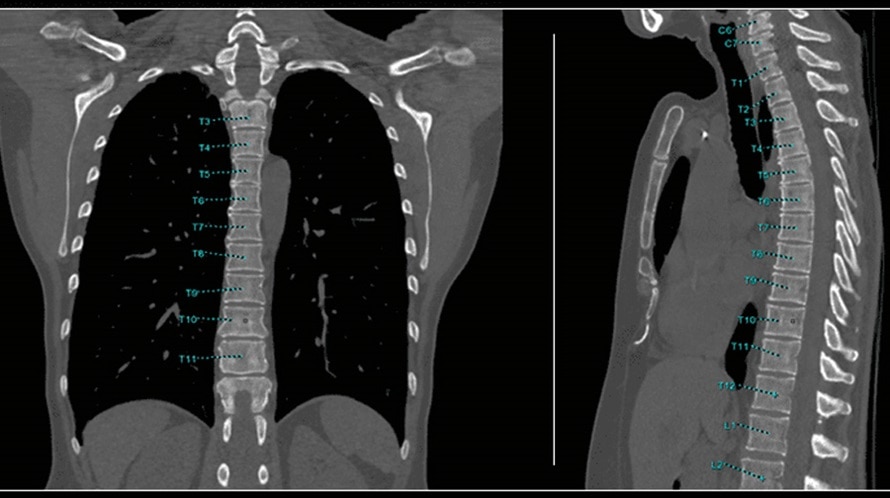

Automated spine labeling with oblique and straightened reformat generation to facilitate reading and reporting

Bone VCAR is a software analysis package utilizing a deep learning algorithm that assists in the analysis and visualization of CT Spine data.

Automated spine labeling

Automated generation of a 3D trace to generate oblique and straightened reformat views

Automated generation of oblique views perpendicular to vertebral bodies and disc spaces

Works on full spine acquisitions as well as limited acquisitions containing segments of the spine